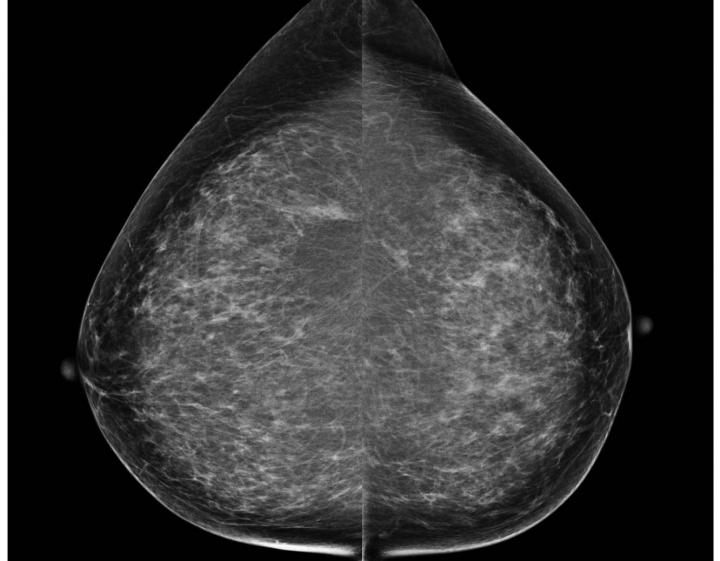

Breast Cancer Mammogram